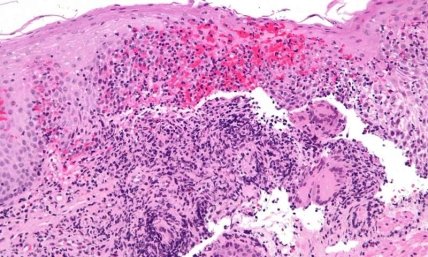

Гистологическая картина пищевода с болезнью Крона